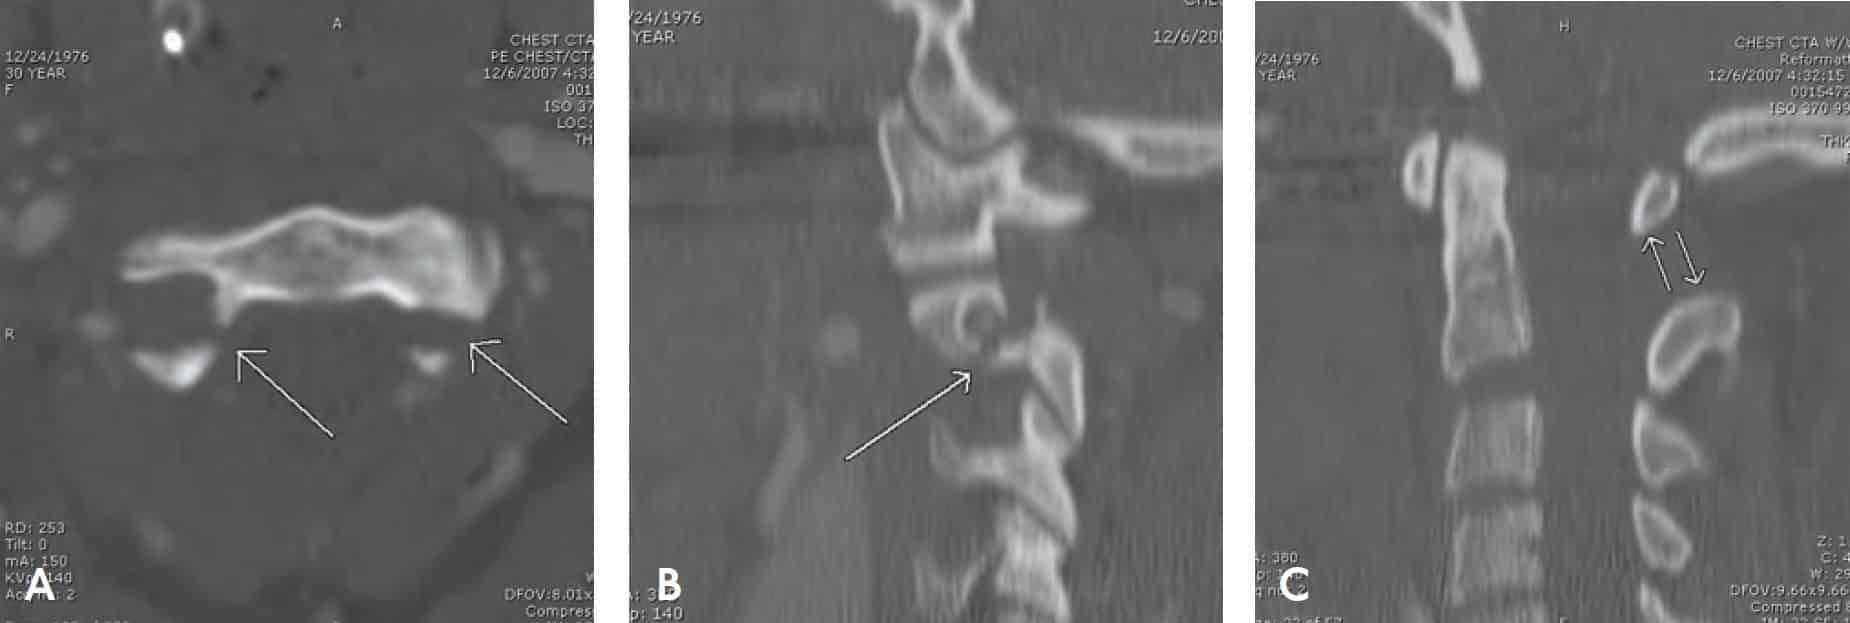

Перелом заднього елемента другого шийного хребця, або так званий перелом шибеника, зачіпає задні елементи C2, частини хребця, розташовані між нижнім і верхнім суглобовими відростками — pars interarticularis (Зобр. 7-6).

Зобр. 7-6 Перелом шибеника (стрілки). Продемонстровано на КТ реконструкціях: A. осьова; B. сагітальна парамедіальна; і C. сагітальна середня лінія. Зверніть увагу на передній кут і надмірну відстань між остистими відростками С1 і С2 (подвійні стрілки)

Цей тип перелому зазвичай спричинений травмою від розтягнення. Переконайтеся, що пацієнтам із цим переломом накладено жорсткий шийний комір відповідного розміру, доки не буде доступна спеціалізована допомога.